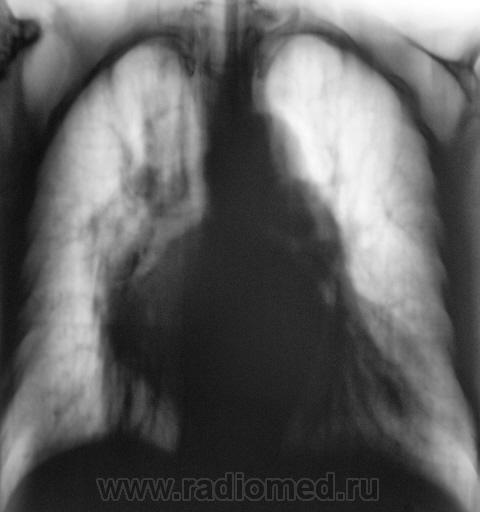

Следующий срез.

На рентгенограммах (в отличии от томо) на верхушке ничего не заметил. А так, похоже на митр. недостаточность.